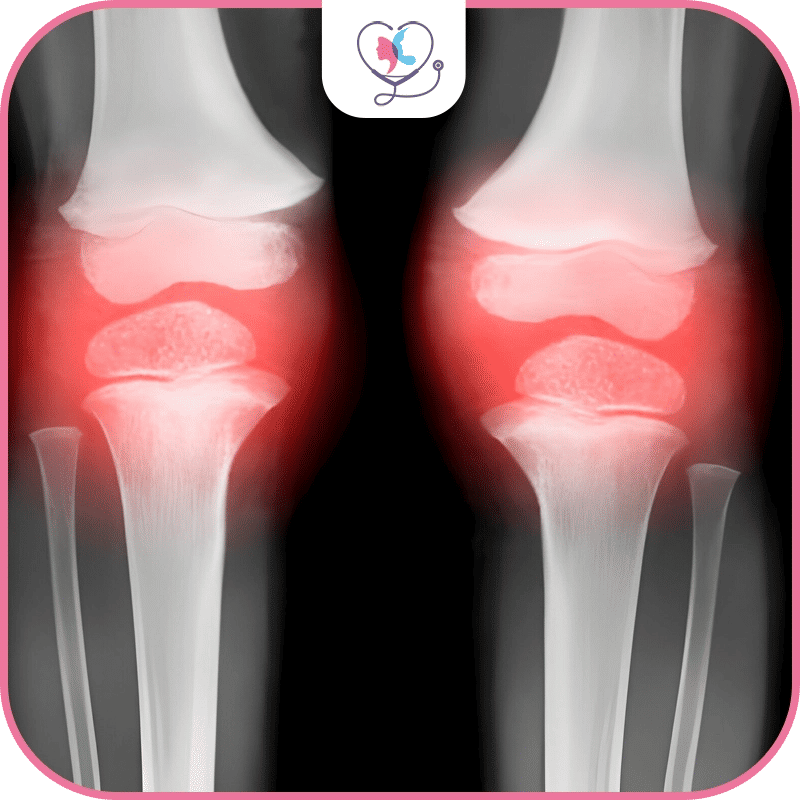

قبل الحديث عن أهمية الكشف المبكر عن التهاب مفاصل الركبة؛ نودّ لفت انتباهك إلى أنّ هذه الحالة تُصيب حوالي 203 شخص من كل 10 آلاف شخص سنوياً، ونظراً لأنّ أعراض هذه الحالة قد تتشابه مع حالات مرضية أخرى فهنا تأتي أهمية التشخيص الدقيق والمبكر للحالة، ويعمل فريق تركيا لاكشري كلنيك على تحقيق ذلك وتقديم طرق العلاج المناسبة.

قد تتسائل لماذا يحدث التهاب مفاصل الركبة؟ حقيقةً إنّ هذه الحالة لا تحدث بصورةٍ مفاجئة، غالباً ما تحدث تدريجياً على فترات زمنية نتيجة تآكل وتلف غضاريف الركبة، إذا ماذا سيحدث بعدها؟ ستجد عظام مفصل ركبتك تحتك ببعضها البعض مما يُسبب لك شعوراً بالألم والانزعاج، مع تدني قدرتك على ممارسة حياتك وأنشطتك المعتادة على غير المعتاد.

كيف أستدلّ على إصابتي بالتهاب المفاصل؟ قد تكون الأعراض التي تشكو منها مؤشراً على ذلك؛ ومنها: ألم المفاصل خاصة بعد بذل مجهود، أو تيبس المفاصل خاصة صباحاً أو في أوقات الراحة، كذلك سماع صوت احتكاك أو طقطقة عند تحريك المفصل، وعدم القدرة على تحريك مفصل ركبتك كالمعتاد، إذن لا تستهِن بصحتك! ما عليك سوى حجز موعدك مع تركيا لاكشري كلنيك.